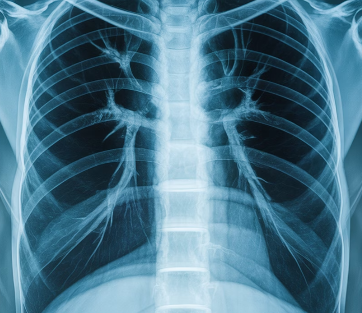

폐암은 조기 발견이 무엇보다 중요한 질환이지만,

초기에는 특별한 통증 없이 조용히 진행되는 경우가 많습니다.

그래서 작은 변화도 놓치지 않는 것이 매우 중요합니다.

오늘은 폐암 초기증상들을 자세하게 정리해 드릴게요.

1. 폐암이 초기 증상이 적은 이유

폐 조직에는 통증을 느끼는 신경이 거의 없어,

종양이 자라더라도 초반에는 큰 불편함이 나타나지 않습니다.